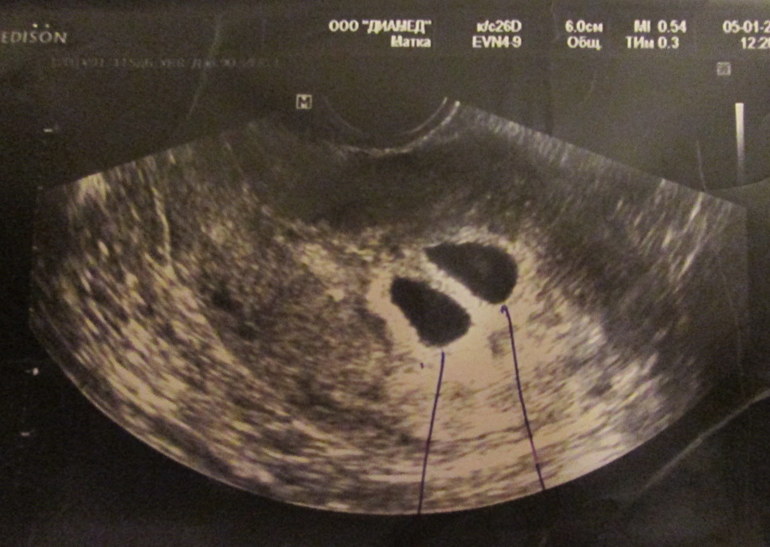

6,01 сходила на Узи поглядеть, что ПЯ в матке. И тут меня ждал сюрпрайз двойня))). Начну с того, что я сама с двойни, моя сестра двойняшка родила королевскую двойню. Первая Б в 2009 была двойня, к сожалению первый плод замер, сделали прерывание на 25 нед. в 2011 родила чудесного мальчишку. Сейчас тянет живот, очень боюсь, просто ужасно боюсь. На узи есть отслойка у одного ПЯ, завтра ложусь на сохранение. Надеюсь все будет хорошо и мы родимся в срок, в августе. Девчонки давайте дружить, у меня куча вопросов и страхов.

А вот наше первое фото: